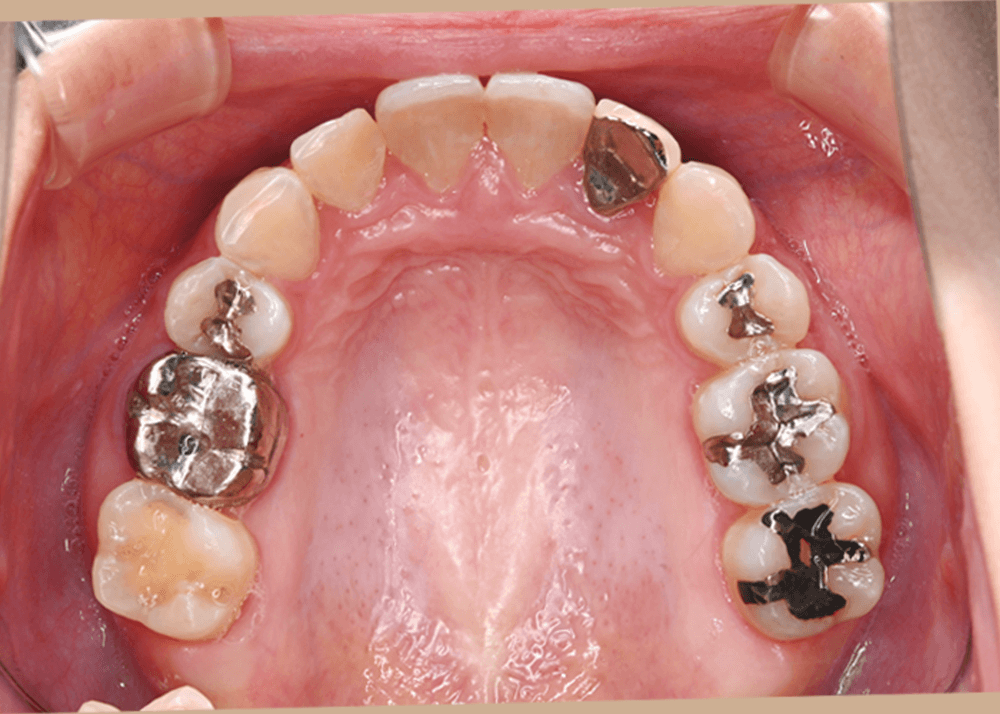

治療前の状態

すでに矯正治療を終えられていたため、歯列に大きなガタつきはなく、上下の歯の咬み合わせも良好でした。

しかし顔貌の観察では以下の特徴が見られました。

側貌(横顔)

上顎前歯が舌側に強く傾斜しており、口唇のサポートが不足していました。

その結果、口元のボリュームが少なく、横顔がやや平坦な印象となっていました。

スマイル時の印象

患者様ご本人も

「笑ったときに歯が奥まって見える」

という違和感を強く感じておられました。

歯並び自体は整っていても、前歯の位置や傾斜によって口元の印象は大きく変化します。